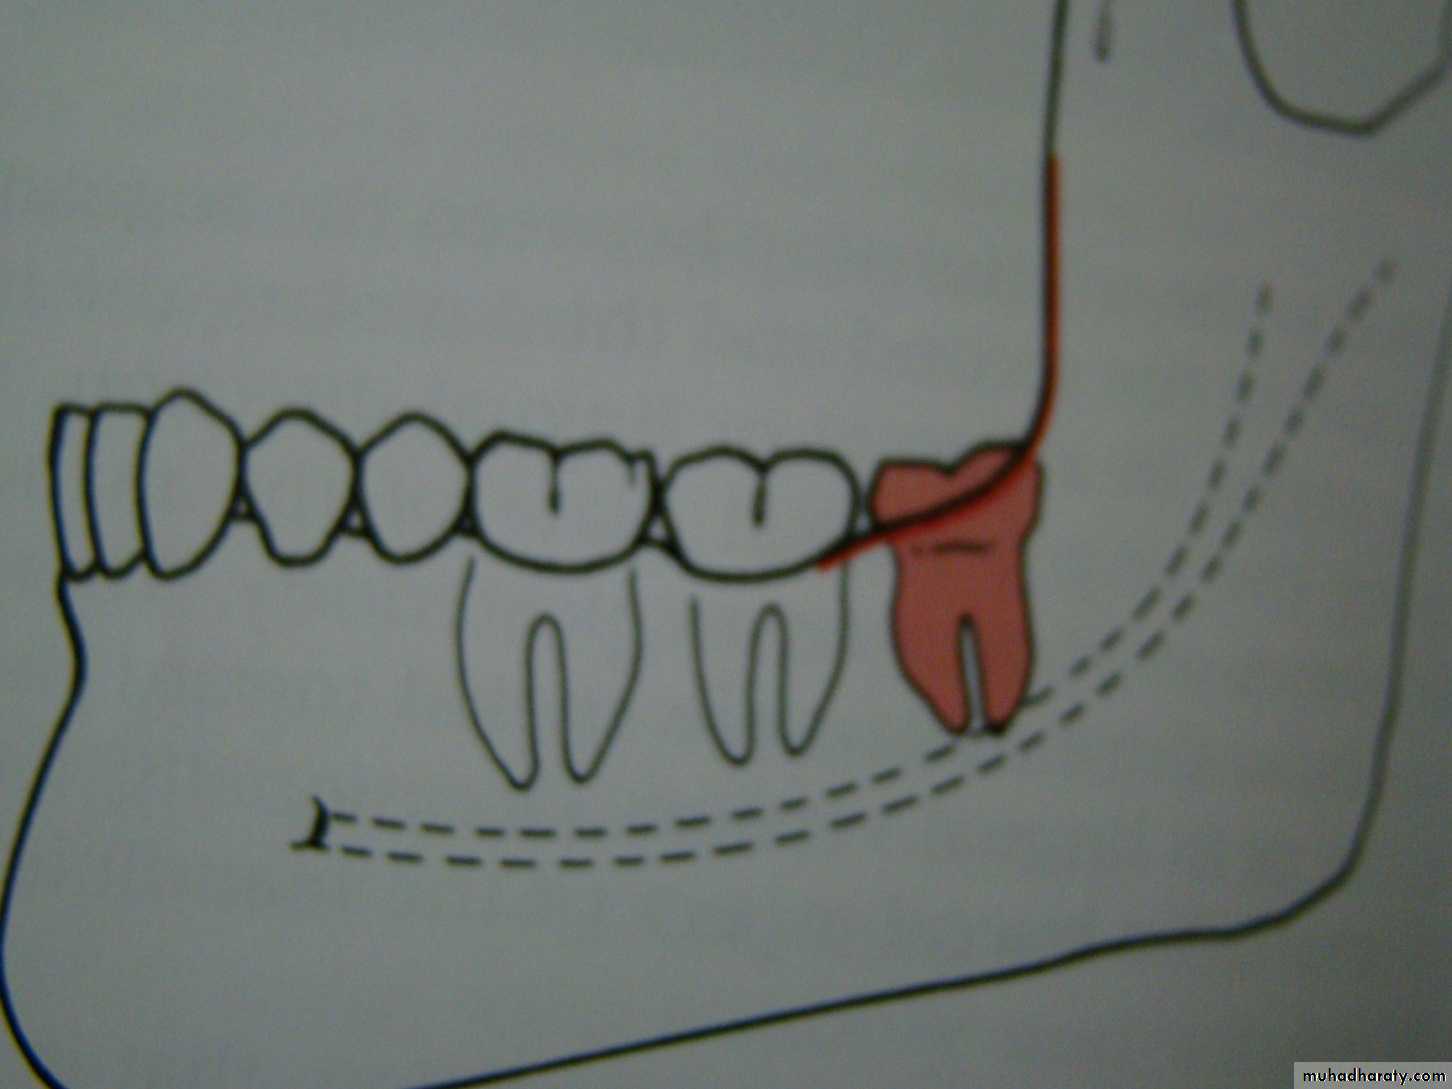

7 - Tooth in the fracture lineE.g Impacted lower third molar may weakens the angle of the mandible and make it more liable to fracture during trauma to the face .